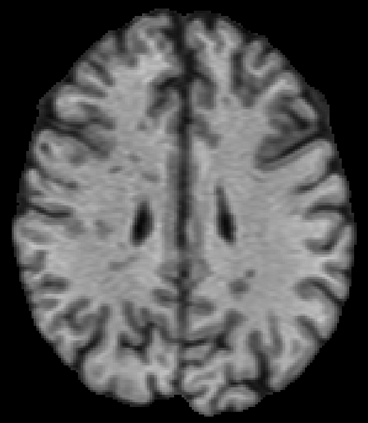

Recently, segmentation methods based on Convolutional Neural Networks (CNNs) showed promising performance in automatic Multiple Sclerosis (MS) lesions segmentation. These techniques have even outperformed human experts in controlled evaluation conditions such as Longitudinal MS Lesion Segmentation Challenge (ISBI Challenge). However state-of-the-art approaches trained to perform well on highly-controlled datasets fail to generalize on clinical data from unseen datasets. Instead of proposing another improvement of the segmentation accuracy, we propose a novel method robust to domain shift and performing well on unseen datasets, called DeepLesionBrain (DLB). This generalization property results from three main contributions. First, DLB is based on a large group of compact 3D CNNs. This spatially distributed strategy ensures a robust prediction despite the risk of generalization failure of some individual networks. Second, DLB includes a new image quality data augmentation to reduce dependency to training data specificity (e.g., acquisition protocol). Finally, to learn a more generalizable representation of MS lesions, we propose a hierarchical specialization learning (HSL). HSL is performed by pre-training a generic network over the whole brain, before using its weights as initialization to locally specialized networks. By this end, DLB learns both generic features extracted at global image level and specific features extracted at local image level. DLB generalization was validated in cross-dataset experiments on MSSEG'16, ISBI challenge, and in-house datasets. During experiments, DLB showed higher segmentation accuracy, better segmentation consistency and greater generalization performance compared to state-of-the-art methods. Therefore, DLB offers a robust framework well-suited for clinical practice.